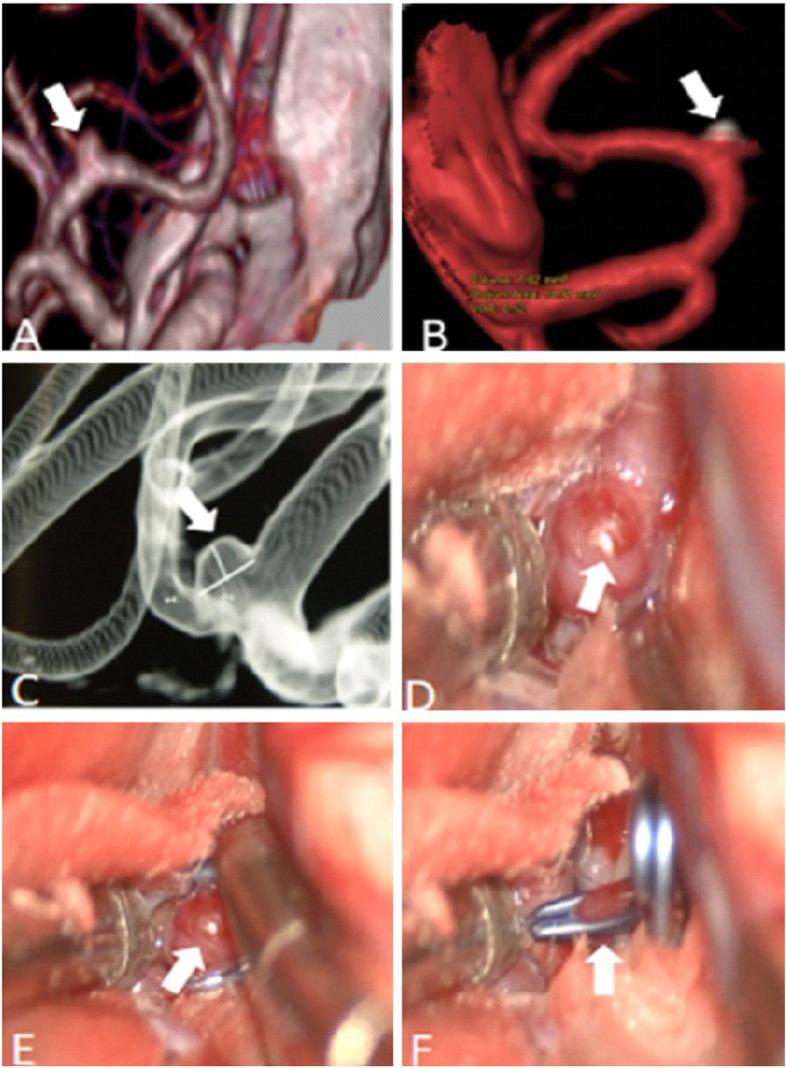

The morphological characteristics detected by 4D-CTA and DSA were consistent in aneurysm location (k = 1.0), shape (k = 0.76), maximum diameter (k = 0.94), aneurysm neck (k = 0.79) and proximity to parent and branch vessels (k = 0.85). 4D-CTA required lower radiation doses (0.32 ± 0.11 mSv) than DSA (0.84 ± 0.37 mSv, P < 0.001). Pulsation was detected in 26 of the 64 unruptured aneurysms, and all underwent neurosurgical clipping or interventional embolization. In aneurysms surgically treated in our hospital, we observed a significant correlation between 4D-CTA findings and surgical evaluation of the aneurysmal wall, in particular the irregular pulsations detected on 4D-CTA have demonstrated to correspond to dark-reddish thinner wall at surgery.

In this proof-of-concept study, 4D-CTA provided real-time, non-invasive preoperative assessments of UIAs comparable to DSA. Moreover, optimal correlation between the irregular pulsation detected by 4D-CTA and the surgical findings support a possible role of this technique to identify aneurysms with a higher risk of rupture.

结果

在这项概念验证研究中,4D-CTA 提供了与 DSA 相当的实时、非侵入性的 UIAs 术前评估。此外,4D-CTA 检测到的不规则搏动与手术发现之间的最佳相关性支持该技术可能用于识别具有更高破裂风险的动脉瘤。